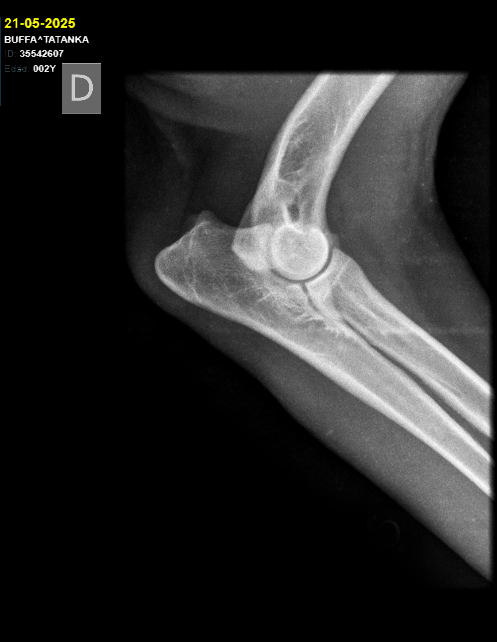

Cadera Codos:

HD A / ED 0/0